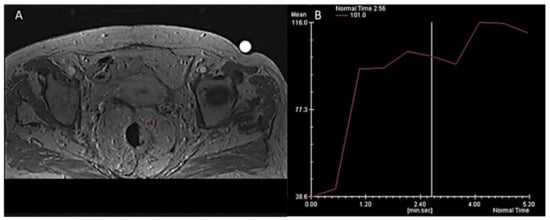

- Petrillo, A.; Fusco, R.; Petrillo, M.; Granata, V.; Bianco, F.; Marzo, M.D.; Delrio, P.; Tatangelo, F.; Botti, G.; Pecori, B.; et al. DCE-MRI Time–Intensity Curve Visual Inspection to Assess Pathological Response after Neoadjuvant Therapy in Locally Advanced Rectal Cancer. Jpn. J. Radiol. 2018, 36, 611–621. [Google Scholar] [CrossRef] [PubMed]

- Petrillo, A.; Fusco, R.; Petrillo, M.; Granata, V.; Sansone, M.; Avallone, A.; Delrio, P.; Pecori, B.; Tatangelo, F.; Ciliberto, G. Standardized Index of Shape (SIS): A Quantitative DCE-MRI Parameter to Discriminate Responders by Non-Responders after Neoadjuvant Therapy in LARC. Eur. Radiol. 2015, 25, 1935–1945. [Google Scholar] [CrossRef] [PubMed] [Green Version]

- Fusco, R.; Petrillo, A.; Petrillo, M.; Sansone, M. Use of Tracer Kinetic Models for Selection of Semi-Quantitative Features for DCE-MRI Data Classification. Appl. Magn. Reson. 2013, 44, 1311–1324. [Google Scholar] [CrossRef]

- Fusco, R.; Granata, V.; Sansone, M.; Rega, D.; Delrio, P.; Tatangelo, F.; Romano, C.; Avallone, A.; Pupo, D.; Giordano, M.; et al. Validation of the Standardized Index of Shape Tool to Analyze DCE-MRI Data in the Assessment of Neo-Adjuvant Therapy in Locally Advanced Rectal Cancer. Radiol. Med. 2021, 126, 1044–1054. [Google Scholar] [CrossRef]